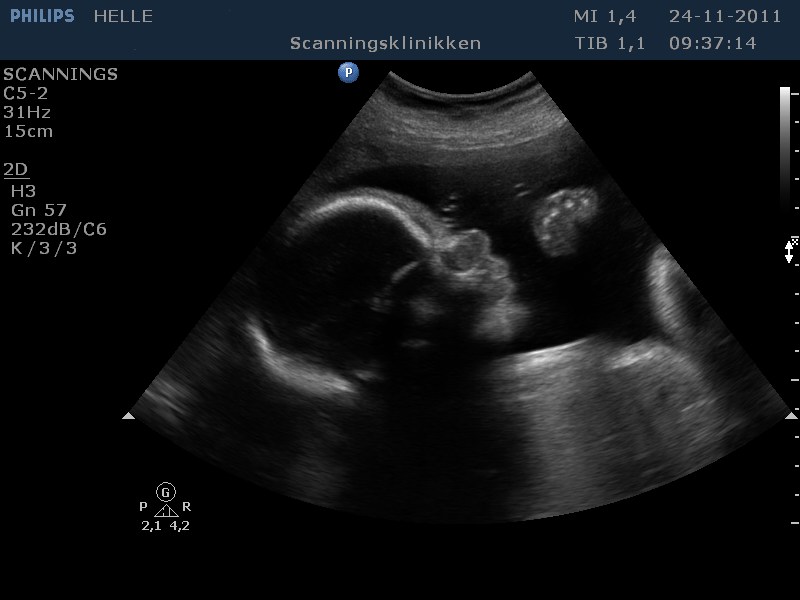

Her går det også godt, - er lige kommet hjem fra en fantastisk 3D scanning. Vores lille pige har det godt og er helt igennem fin! SÅ SØD! Hun har indhentet den manglende vægt og ligger nu lige over gennemsnittet med ca. 1500 g, så det er dejligt!

Jeg er blevet sygemeldt grundet lavt blodtryk, og jeg tror at dette også har haft en positiv indvirkning på hendes vægt. På mandag skal vi til vækstscanning på Hvidovre, - så må vi se om de er enige.